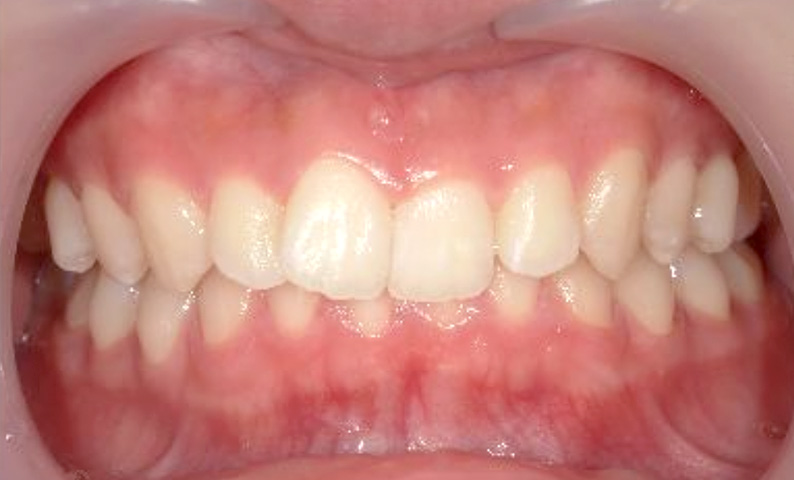

症例_002 上下顎の部分矯正

治療期間:7ヶ月金額:54万円+税女性前歯のガタガタ出っ歯八重歯

| Before | After |

|---|---|

|